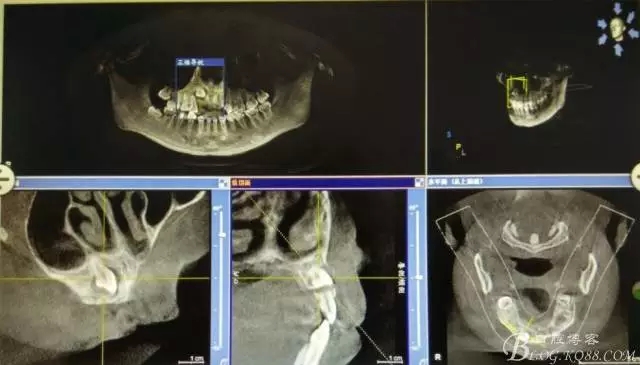

病例資料: 患者、柴xx、女、16歲。??茩z查及病歷如下圖: 患者同意我院正畸科建議,遂轉(zhuǎn)診倒外科。術(shù)前簽知情同意書。 治療過程: 圖1.術(shù)前的CBCT檢查:13阻生,疑為含牙囊腫??v剖面顯示12牙根吸收至根尖1/3。 圖2.局部麻醉下 。行唇側(cè)弧形切口,12松動(dòng)不到1°。 圖3.翻瓣、暴露骨面。 圖4.去骨、 暴露13牙冠 圖5.去骨、逐漸顯露13。 圖7.拔除13. 圖8.摘除囊壁 圖9.必須完整剝離囊壁。 圖10.摘除囊壁后形成的骨腔 圖11.超聲骨刀12根尖倒預(yù)備 圖13. 消毒棉球骨腔內(nèi)隔濕血液,紙尖干燥倒預(yù)備好的根管 圖14. 紙尖無血即可 圖15。MTA倒充填 圖16.骨腔填塞膠原蛋白海綿 圖17.拔除的13及摘除的囊壁 圖18.縫合 圖19.術(shù)后x線根尖片影像:MTA封閉根尖